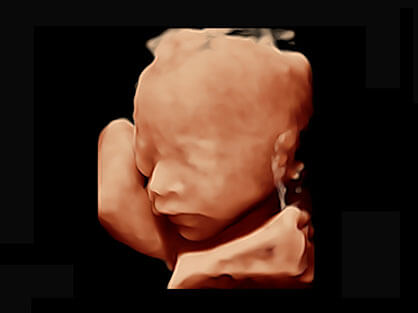

可同时显示组织结构表面和内部的轮廓信息,达到透视效果,为临床提供更丰富的诊断信息。

宽频带腹部凸阵探头和腹部容积探头、大角度腔内探头和腔内容积探头、独特的生殖专用曲柄探头,为妇产应用提供全面诊疗方案。